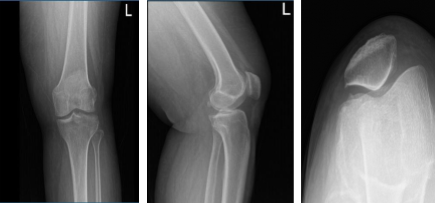

She had an X-ray result, we reviewed and discussed it. X-ray results showed normal radiographs considering her age, severity of pain, and inability to do activities of daily living and work, that’s the time we agreed to go with 3 tesla MRI of left knee to see the reason behind it. By this time, she will take tramadol until her next visit with an MRI result.

Left knee x-ray complete with patella